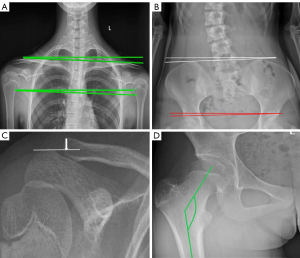

Photographs were taken by 2 technicians with over 5 years of relevant working experience. All indexes were measured by 2 clinicians with 3 years of relevant working experience and were performed on the picture archiving and communication systems (PACS; Donghua iMedical PACS 2020; Beijing, China), including the Cobb angle, clavicular angle (CA) (6), glenoid obliquity angle, acromioclavicular joint deviation or offset (14), femoral neck-shaft projection angle, iliac obliquity angle (IO) (15), acetabular obliquity angle, coronal width ratio of the left and right pelvis (L/R) (16), coronal trunk deviation distance, and spinal deformity deviation distance on the sagittal plane (17,18) (Figures 2,3). There was no missing data.

AIS was defined as a Cobb angle >10°. A CA ≥2° was defined as shoulder imbalance, and the left side being higher was considered positive (5). An IO ≥2° was defined as pelvic imbalance, and the left side being higher was recorded as positive (15). A coronal width ratio of the left and right halves of the pelvis (L/R) <1 represented a right rotation of the pelvis, and an L/R ratio <1 reflected a left rotation of the pelvis (16). All data were evaluated by researchers without the use of automatic software programs.